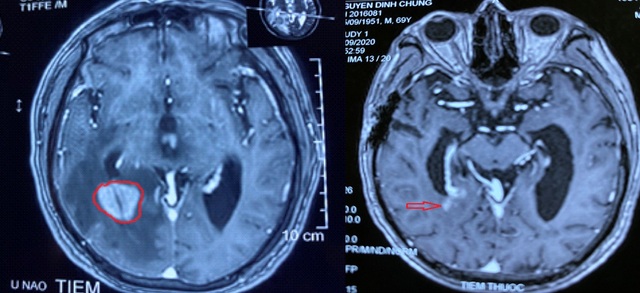

Hình ảnh cộng hưởng từ sọ não trước và sau điều trị.

Cuối tháng 8, bệnh nhân được chuyển đến Trung tâm Ung bướu của Bệnh viện 19-8 với các biểu hiện đau đầu nhiều, đau âm ỉ liên tục, đau tăng dần, kèm theo có nôn, buồn nôn, xuất hiện cơn co giật tăng dần, rối loạn ý. Tại đây, bệnh nhân đã được các bác sĩ khám và chụp phim cộng hưởng từ sọ não, phát hiện khối u não kích thước 36x30x28mm, gây phù não diện rộng xung quanh. Bệnh nhân được chuẩn đoán là u lympho ác tính không hodgkin biểu hiện và được cứu chữa kịp thời.

Sau 20 ngày xạ trị, bệnh nhân tỉnh hoàn toàn, không đau đầu, không nôn, không buồn nôn, đại tiểu tiện tự chủ, tự ngồi dậy và ăn uống vận động sinh hoạt bình thường. Kiểm tra lại bằng cộng hưởng từ sọ não thấy khối u tan gần hết, hết phù não.